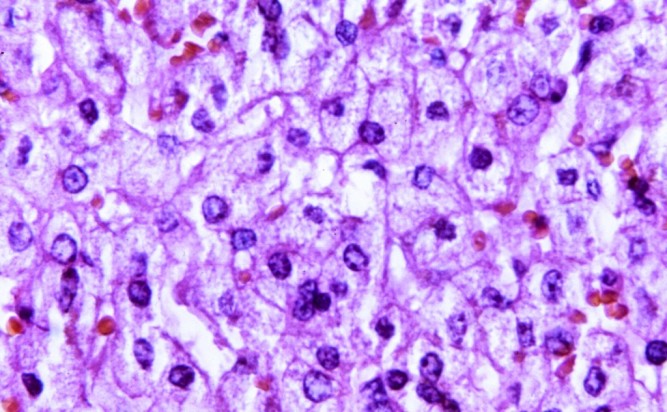

Черният дроб се състои от хепатоцити - чернодробни клетки, които произвеждат различни ензими. Маркерите ALT (аланин аминотрансфераза) и AST (аспартат аминотрансфераза) в кръвният ви тест са ензими, необходими за осигуряване на енергия и поддържане на здравето.

Ако например човек има вирусен хепатит или токсичен хепатит, или някои промени в метаболитния процес в него, то хепатоцитите започват да се "бунтуват" и да се променят структурно. В резултат на това повече ензими преминават през клетъчната мембрана, което води до повишаване на нивата на ALT или AST."

Микрофотографско увеличение 440X на чернодробна тъкан, оцветена с хематоксилин и еозин (H&E) / снимка: rawpixel.com

Микрофотографско увеличение 440X на чернодробна тъкан, оцветена с хематоксилин и еозин (H&E) / снимка: rawpixel.com